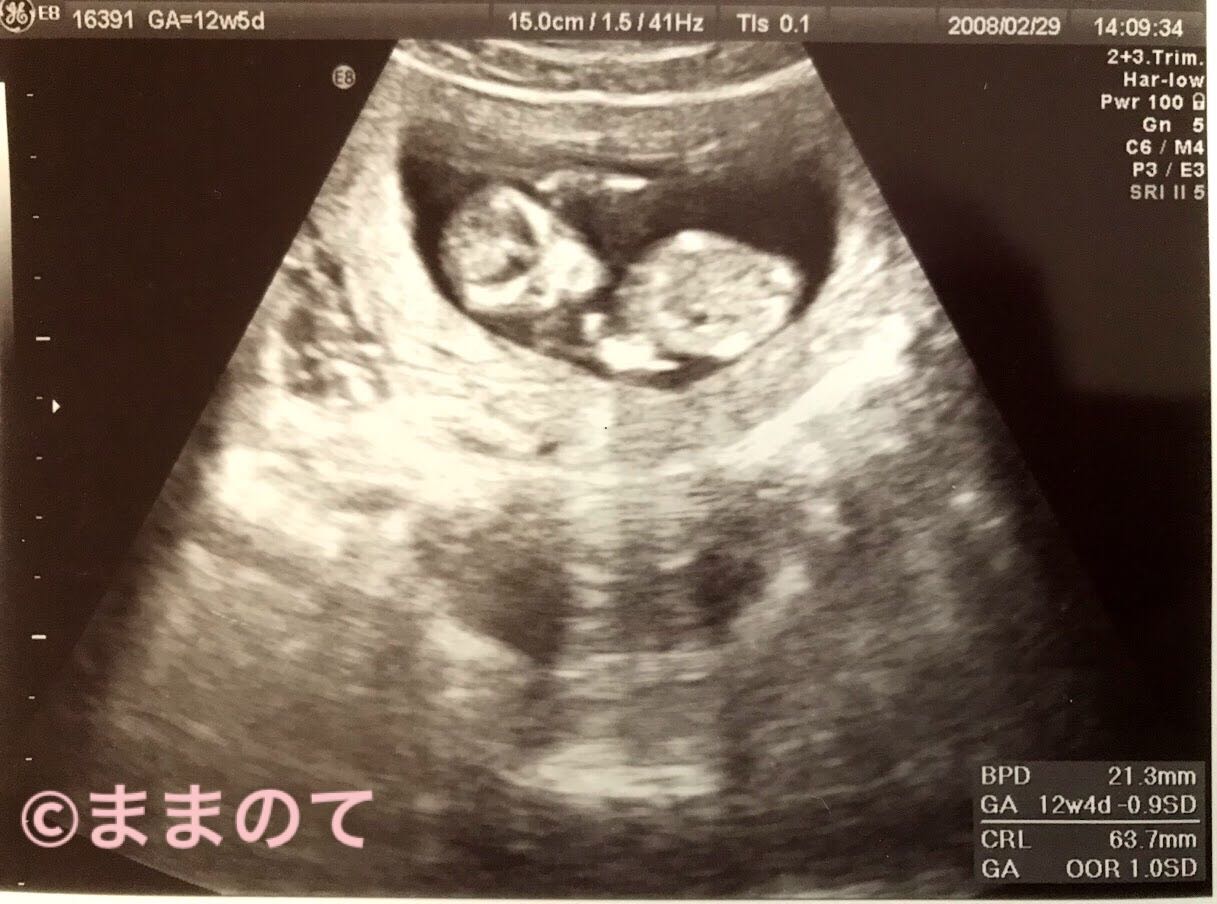

妊娠12週の赤ちゃんのエコー画像

12週4日のエコー写真です。正面に向けた顔には、目と口がはっきりと確認できます。上にあげた手の先には、指がうっすらと確認できます。まるで頭を抱えているような仕草が愛らしいですね。このころの頭部は頭蓋内が透けてみえます。